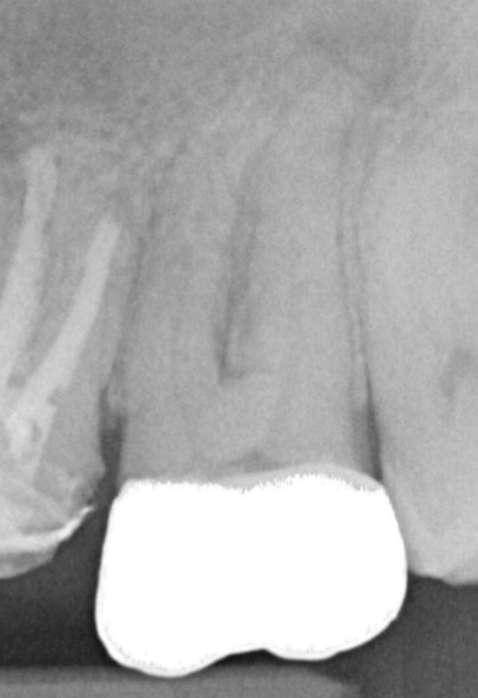

Röntgenologischer Befund: Zahn 27 weist eine apikale Aufhellung im Sinne einer chronischen apikalen Parodontitis auf (Abbildung 6).

Abbildung 6: Präoperative diagnostische Aufnahme

Die primäre endodontische Behandlung des Zahns 27 wurde ebenfalls in einer Sitzung durchgeführt. Nach der Trepanation erfolgte die initiale intrakoronale Diagnostik und Darstellung der vier Kanalorifizien mithilfe langschaftiger Rosenbohrer.

Zur koronalen Erweiterung der Kanäle wurde eine EdgeFile X7 der Größe 17.06 eingesetzt. Die Erstellung des Gleitpfads konnte rein mechanisch durchgeführt werden. Hierzu wurden EdgeFile X7 der Größe 17.04, 17.06 in alternierender Weise bis zum Erreichen der näherungsweise röntgenologisch bestimmten vorläufigen Arbeitslänge eingesetzt. Nach elektrometrischer Bestimmung der Arbeitslänge mit C-Pilot Feilen der Größe 8 und 10 erfolgte die weitere Präparation mit EdgeFile X7 der Größe 20.06, 25.06 und 30.06. Die Kanäle wurden nach der finalen Aufbereitung für 60 Sekunden mit 17% EDTA gespült. Die Abschlussspülung erfolgte schallaktiviert mit 6% NaOCl. Eine Masterpointaufnahme diente zur Verifizierung der Aufbereitung und der Passung der angepassten Guttaperchaspitzen (Abbildung 7). Nach Trocknung mit Mikroabsaugung und Papierspitzen wurden alle Kanäle in warm vertikaler Fülltechnik mit biokeramischem Sealer obturiert (Abbildung 8). Der adhäsive Verschluss erfolgte mit Bulk Fill Flow Komposit (Abbildung 9).

Abbildung 7: Masterpointaufnahme